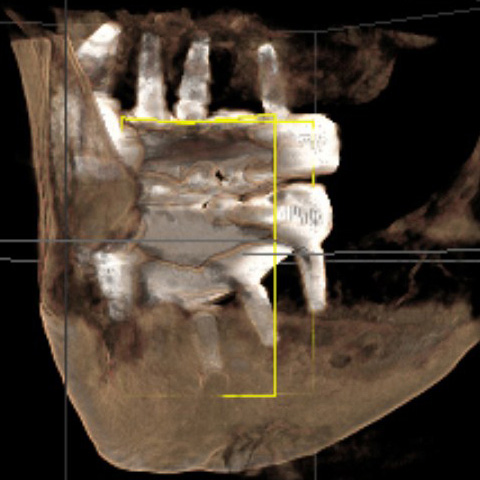

After reviewing CBCT and additional high definition xrays of each implant, a prosthodontist with 40 years experience wrote in his report:

"... the last implant on the lower right side has practically no bone, the last implant on the lower left has about 70-80% bone loss. Both implants should be removed. One implant in the middle is not being used ... "

There are several issues with all of the implants, from problems with their locations, problems with mismatched heights from one implant to another, problems with their depth requiring gum grafts as there is no attached gingiva, problems with two of the upper implants apparently touching each other per periodontist report, a few other issues, and all seem to have some level of bone loss around the implants.

The near total lack of bone at the right lower rear implant, and all the other problems with the implants, already existed when the first periodontist took a CBCT and xrays on October 9, 2024, less than one month after Bansal said everything was perfect. Clearly all those problems did not magically develop overnight.